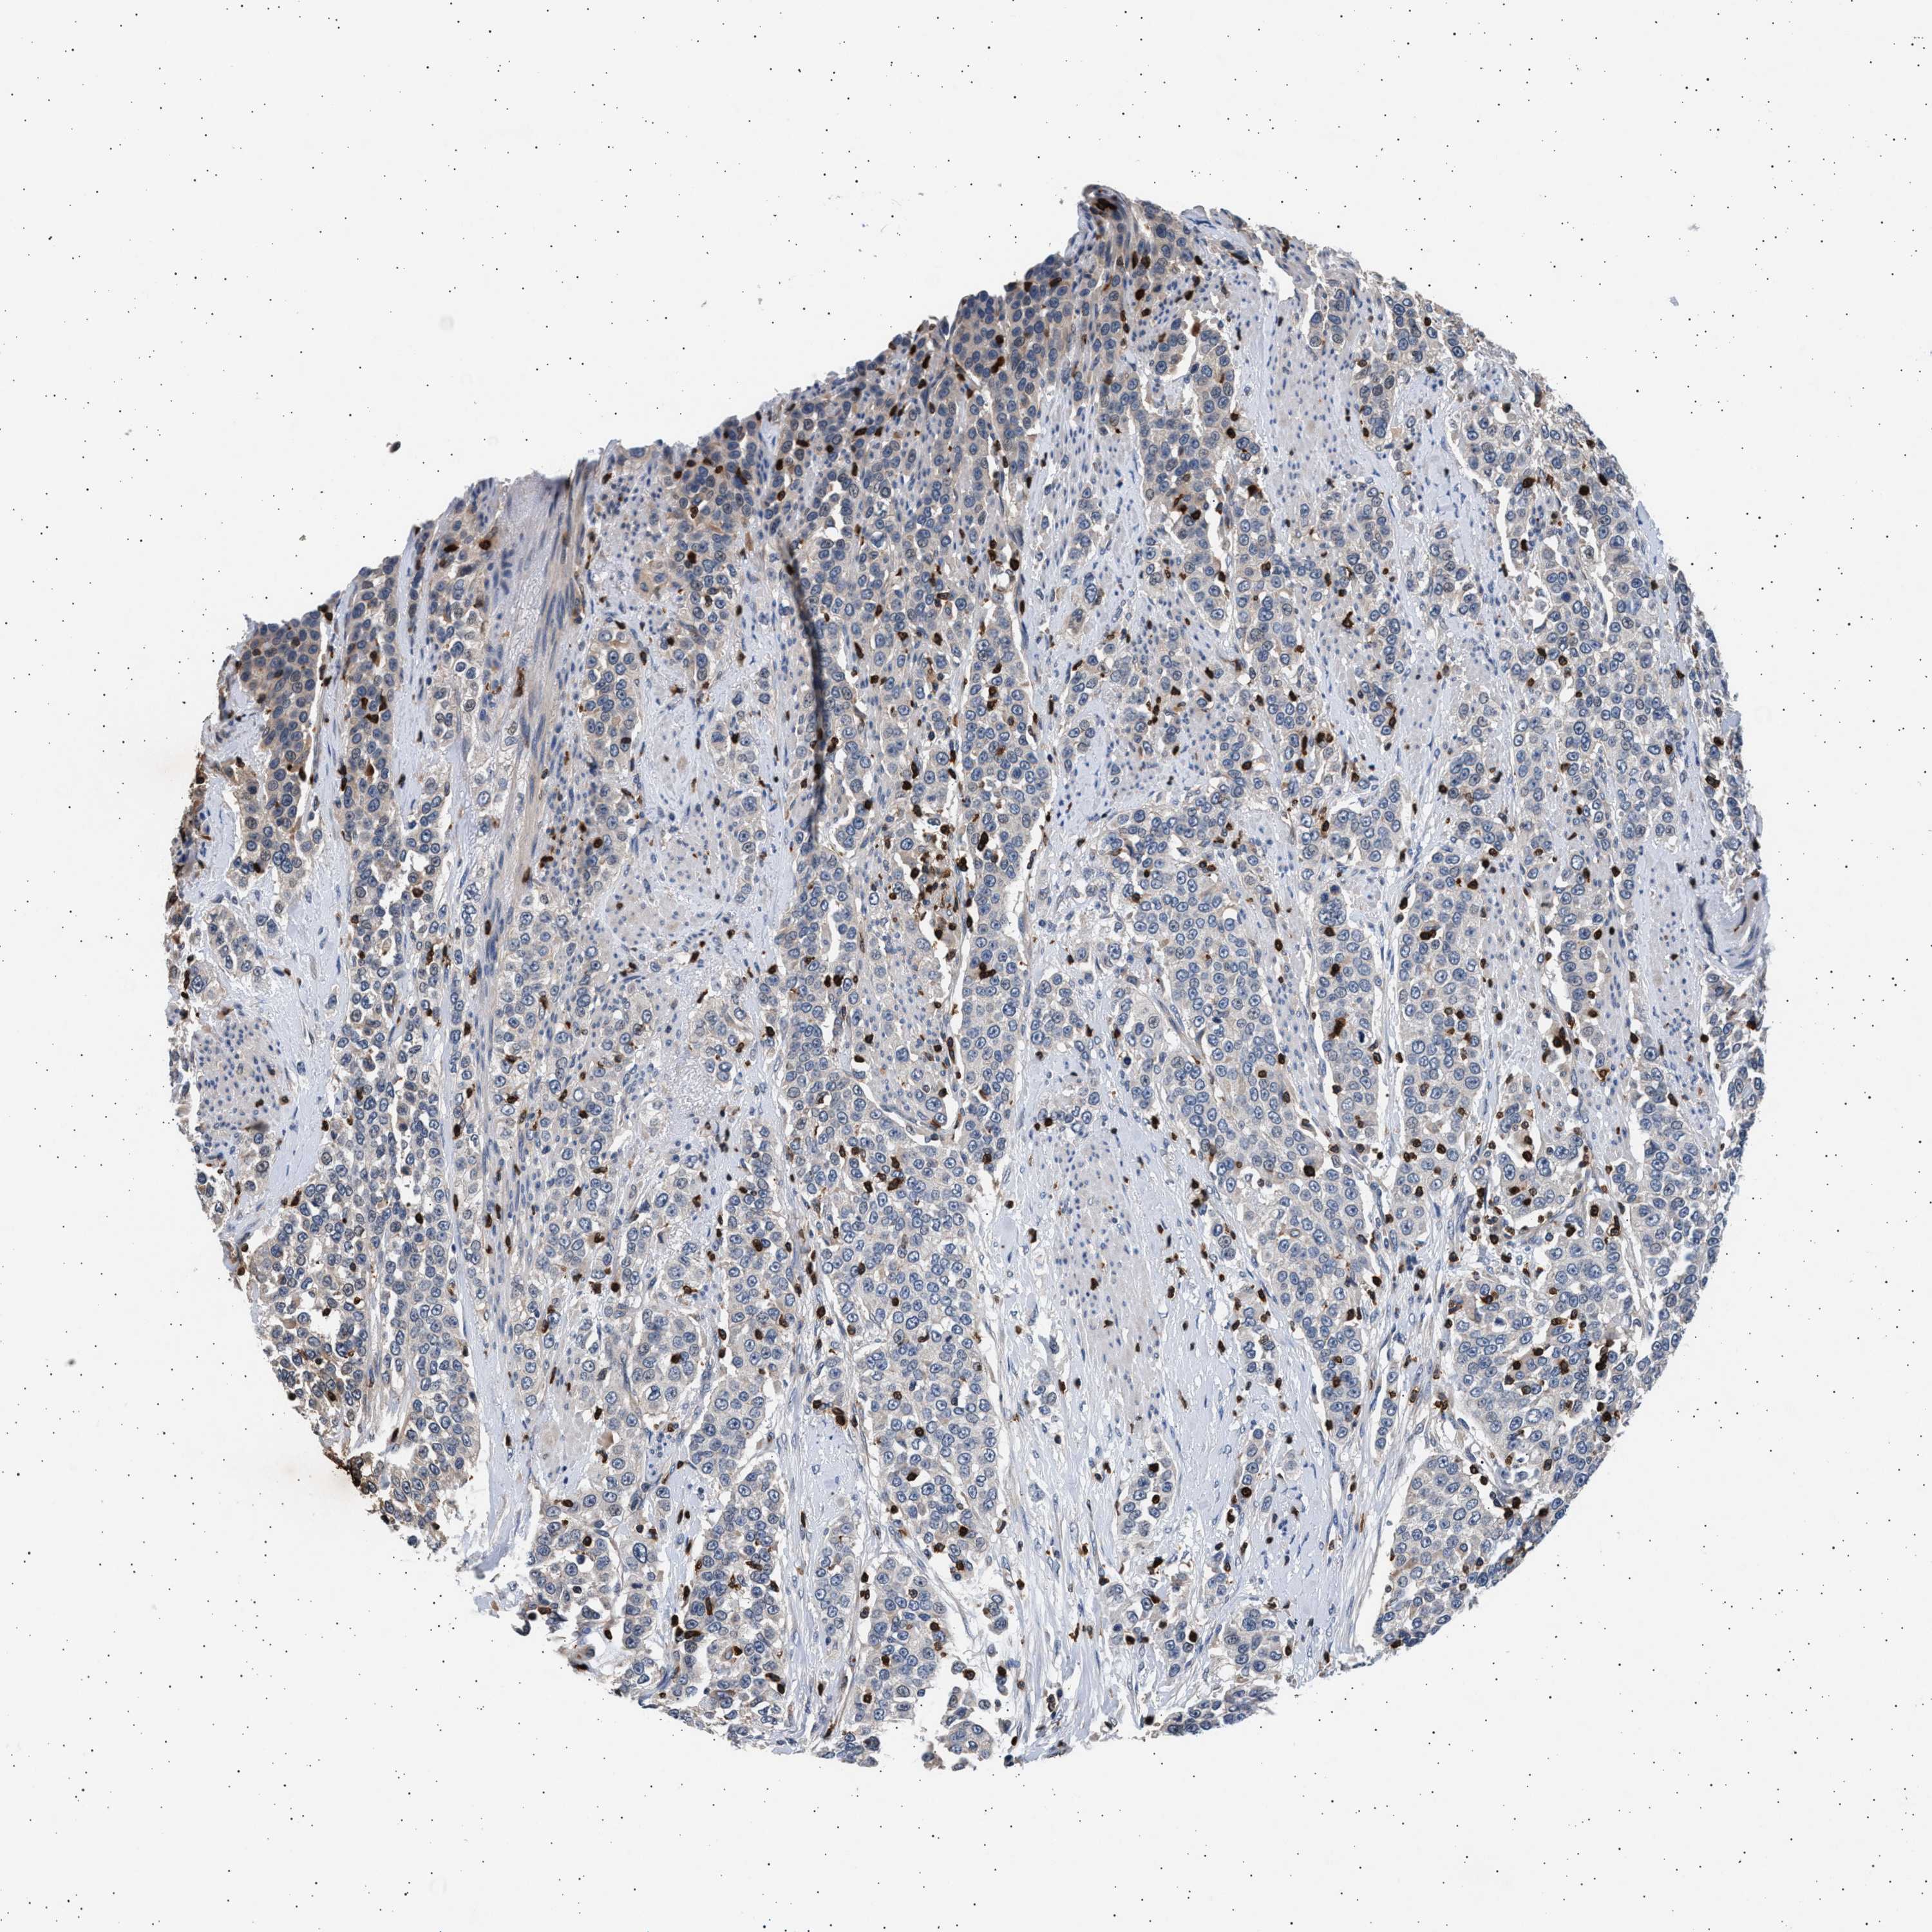

UROTHELIAL CANCER - Protein expressioni

A mouse-over function shows sample information and annotation data. Click on an image to view it in a full screen mode. Samples can be filtered based on level of antibody staining by selecting one or several of the following categories: high, medium, low and not detected. The assay and annotation is described here.

Antibody stainingi

Antibody staining in the annotated cell types in the current human tissue is reported as not detected, low, medium, or high, based on conventional immunohistochemistry profiling in selected tissues. This score is based on the combination of the staining intensity and fraction of stained cells.

Each image is clickable and will lead to virtual microscopy that enables deeper exploration of all samples and also displays staining intensity scores, fraction scores and subcellular localization as well as patient and tissue information for each sample.

Antibody HPA005788

Antibody CAB022073

Staining

High

Medium

Low

Not detected

Intensity

Strong

Moderate

Weak

Negative

Quantity

>75%

75%-25%

<25%

None

Location

Nuclear

Cytoplasmic/membranous

Cytoplasmic/membranous,nuclear

Urothelial carcinoma, NOS